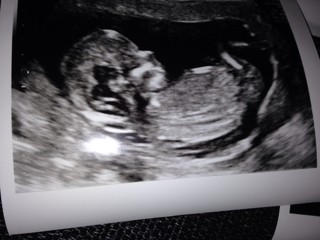

Mój 7 cm skarb :)

ImageUploadedByForum BabyBoom1448913055.449594.jpg

19,1 KB · Wyświetleń: 78